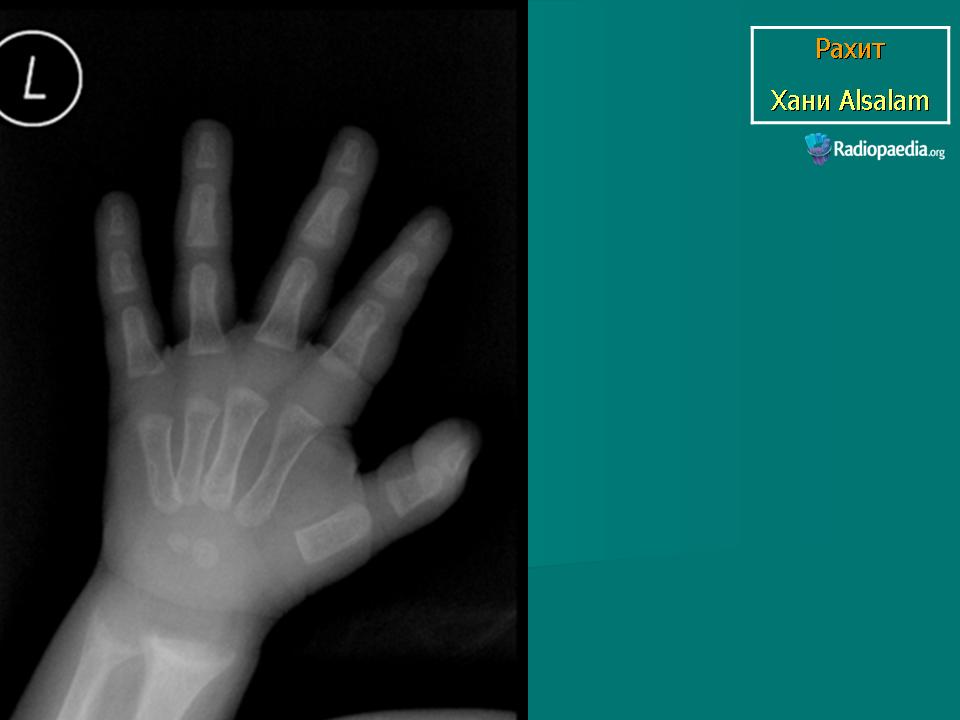

Рентгенологическое исследование позволяет уточнить диагноз, выявить тяжесть заболевания рахитом, стадию болезни, динамику процесса, действенность терапевтических средств.

Одним из первых признаков обеднения костей солями кальция является остеопороз костей, их малая контрастность. Патология энхондрального окостенения на ранних стадиях болезни проявляется в виде небольшого разрыхления зоны предварительного обызвествления, особенно в ее средней части. На уровне росткового хряща возникают участки более светлых включений. Постепенно четкость зоны роста теряется и на высоте цветущего рахита граница между эпифизарным хрящом и метафизарной костью исчезает, костные балочки свободно, в виде отдельных волосков, кисточки или бахромы, заканчиваются по направлению к эпифизу и образуется широкая, неоднородная рахитическая зона. Метафиз увеличивается в диаметре и приобретает характерную бокаловидную форму. Ввиду продолжающегося роста эпифизарное ядро все дальше отодвигается от метафиза, прозрачная для рентгеновских лучей рахитическая зона увеличивается. Ядро окостенения эпифиза также поротично, прослеживаются только наиболее толстые трабекулы, контуры его неровны, особенно со стороны, обращенной к метафизу. В очень тяжелых случаях тень ядра может полностью исчезнуть.